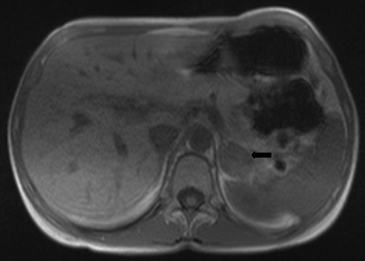

La secuencia gradiente fuera de fase se reconoce porque existe pérdida de señal en la periferia de los órganos en donde contactan con el tejido adiposo, produciéndose un halo negro que rodea a los órganos como si estuvieran dibujados con "tinta china", lo que es evidente en las glándulas suprarrenales, debido a que están inmersas en tejido adiposo y es esa interfase entre la glándula y el tejido adiposo que la rodea que produce este artefacto de cancelación (Figura 13).

Figura 13. Glándula suprarrenal derecha normal. Corte axial de RM ponderada en T1 "fuera de fase", donde se demuestra un halo hipointenso en el margen de la glándula suprarrenal, el característico artefacto en "tinta china". Se ha estimado que existiría una relación lineal inversa entre la caída de señal y el contenido lipídico intracitoplasmático. Sin embargo la intensidad de la caída de señal también depende de la relación grasa-líquido dentro del voxel, puesto que en un voxel que sólo contenga grasa (como en el caso de los mielolipomas que sólo tienen grasa macroscópica) no se demostraría caída de señal en secuencia fuera de fase pues no existen protones de agua que cancelen la señal. Sin embargo hay que señalar que existen adenomas pobres en lípidos y estos muestran un comportamiento similar al de una lesión partes blandas de manera que hay escasa caída de señal en secuencia fuera de fase, por lo que no es posible su diferenciación con esta técnica.